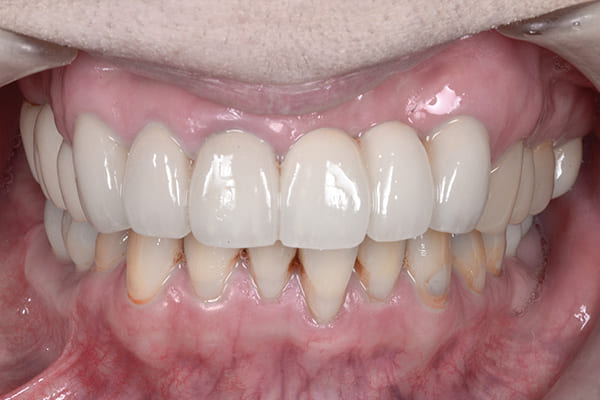

治療後の状態

こちらが最終的な補綴物が入った状態です。

見た目が大きく改善されたことで患者様もとても満足され、さらにしっかりと噛めるようになったことを大変喜ばれていました。